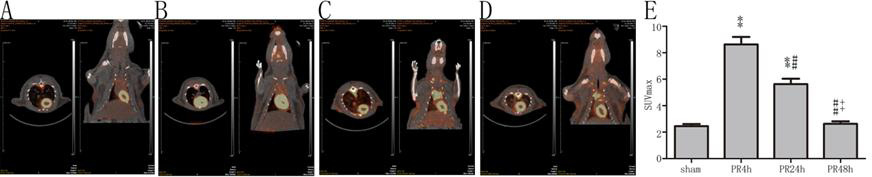

PR 4 h及PR 24 h组大鼠心肌SUVmax较sham组均显著升高(均P < 0.01,图 2),PR 24 h组低于PR 4 h组(P < 0.01),PR 48 h组与sham组比较差异无统计学意义(P > 0.05)。

| A:sham组(n=6);B:PR 4 h组(n=9);C:PR 24 h组(n=9);D:PR 48 h组(n=7);E:SUVmax的比较;与sham组比较,aP < 0.01;与PR 4 h组比较,bP < 0.01;与PR 24 h组比较,cP < 0.01 图 2 各组大鼠心肌葡萄糖代谢 Figure 2 Myocardial glucose metabolism of rats in each group |

生理情况下,心肌能量主要来自脂肪酸和葡萄糖代谢,受损心肌脂肪酸代谢下降,而葡萄糖代谢明显增强[16]。Mcnulty等[17]在心肌缺血模型中发现受损心肌葡萄糖代谢为正常心肌的6.6倍;有研究者认为受损心肌对葡萄糖的偏爱是因为葡萄糖产能耗氧更少[18];也有研究者认为葡萄糖酵解增强、产生的能量用以促进内质网对钙的转移、减轻钙超载[19]。本研究的CA模型中,ROSC 4 h心肌葡萄糖代谢为正常心肌5倍,而在48 h时已降至正常水平,ROSC后心肌葡萄糖代谢增强可能是心肌代谢受损、能量产生障碍的代偿反应。